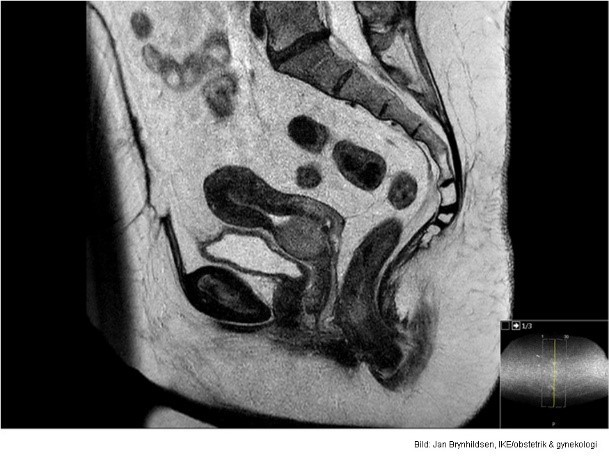

Vad visar bilden?

Normalt cervixepitel

Cervixcancer